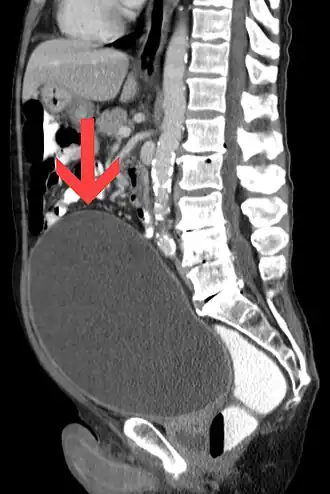

El examen físico muestra una masa en el bajo vientre, por encima del pubis, redondeada, extendida y con un sonido mate a la percusión.

La más frecuente de las complicaciones es la infección urinaria: cistitis primeramente y posteriormente pielonefritis. Cuando es crónica, la retención provoca una distensión de la vejiga con atonía del detrusor, hipertrofia del detrusor o formación divertículos vesicales. La retención urinaria podría provocar un reflujo de la orina hacia los riñones, que causaría una hidronefrosis.